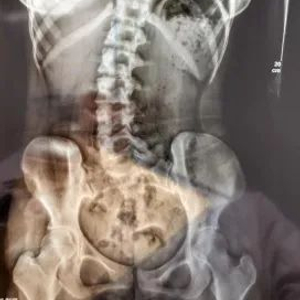

18岁的小邹姑娘,在学习久坐后会常常出现腰痛,脖子伏案久了会有一点酸,近期酸痛情况逐渐严重,遂来到广医三院中医科就诊。经过x光检查发现其腰椎向右侧弯、旋转,并以腰2椎体为中心向右侧弯,Cobb角约10°,脊柱向右发生明显侧弯。  小邹的脊柱明显侧弯